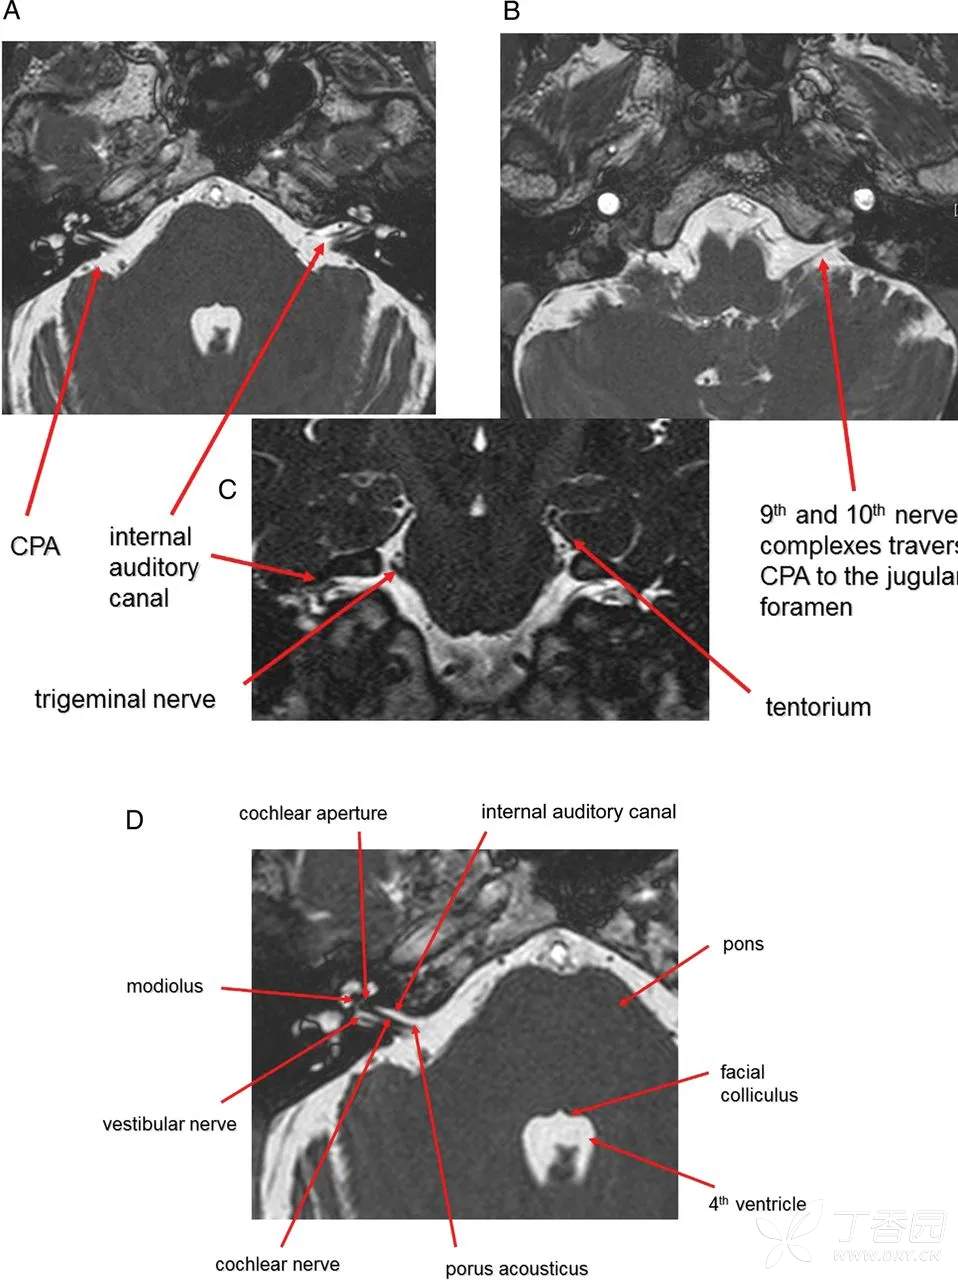

脑桥小脑角池

脑桥小脑角池 cistern of pontocerebellar angle 又名桥池侧突,为桥池向外侧的延续。其前外侧界为颞骨岩部的后内侧壁,后界为小脑中脚和小脑半球,内侧界为脑桥基底部或延髓上外侧部。第四脑室外侧孔开口于此池,面神经和前庭蜗神经经此池入内耳道,小脑下前动脉和迷路动脉也越经此池。

听神经瘤可使脑桥小脑角池内出现肿块影并伴有内耳门、内耳道扩大或形态改变等。